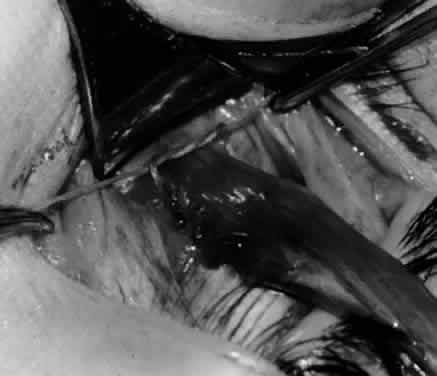

Fig. 7. A Westcott scissor is used gently to open a space beneath the elevated inferior oblique muscle and allow placement of a Green muscle hook.

Fig. 8. The Green muscle hook is placed beneath the belly of the inferior oblique muscle, and the eye is retracted nasally.